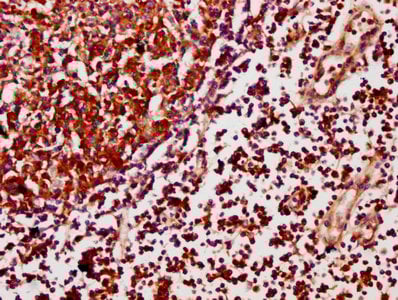

IHC (Immunohistochemistry)

(IHC image of AAA235020 diluted at 1:500 and staining in paraffin-embedded human lymph node tissue performed on a Leica BondTM system. After dewaxing and hydration, antigen retrieval was mediated by high pressure in a citrate buffer (pH 6.0). Section was blocked with 10% normal goat serum 30min at RT. Then primary antibody (1% BSA) was incubated at 4°C overnight. The primary is detected by a biotinylated secondary antibody and visualized using an HRP conjugated SP system.)